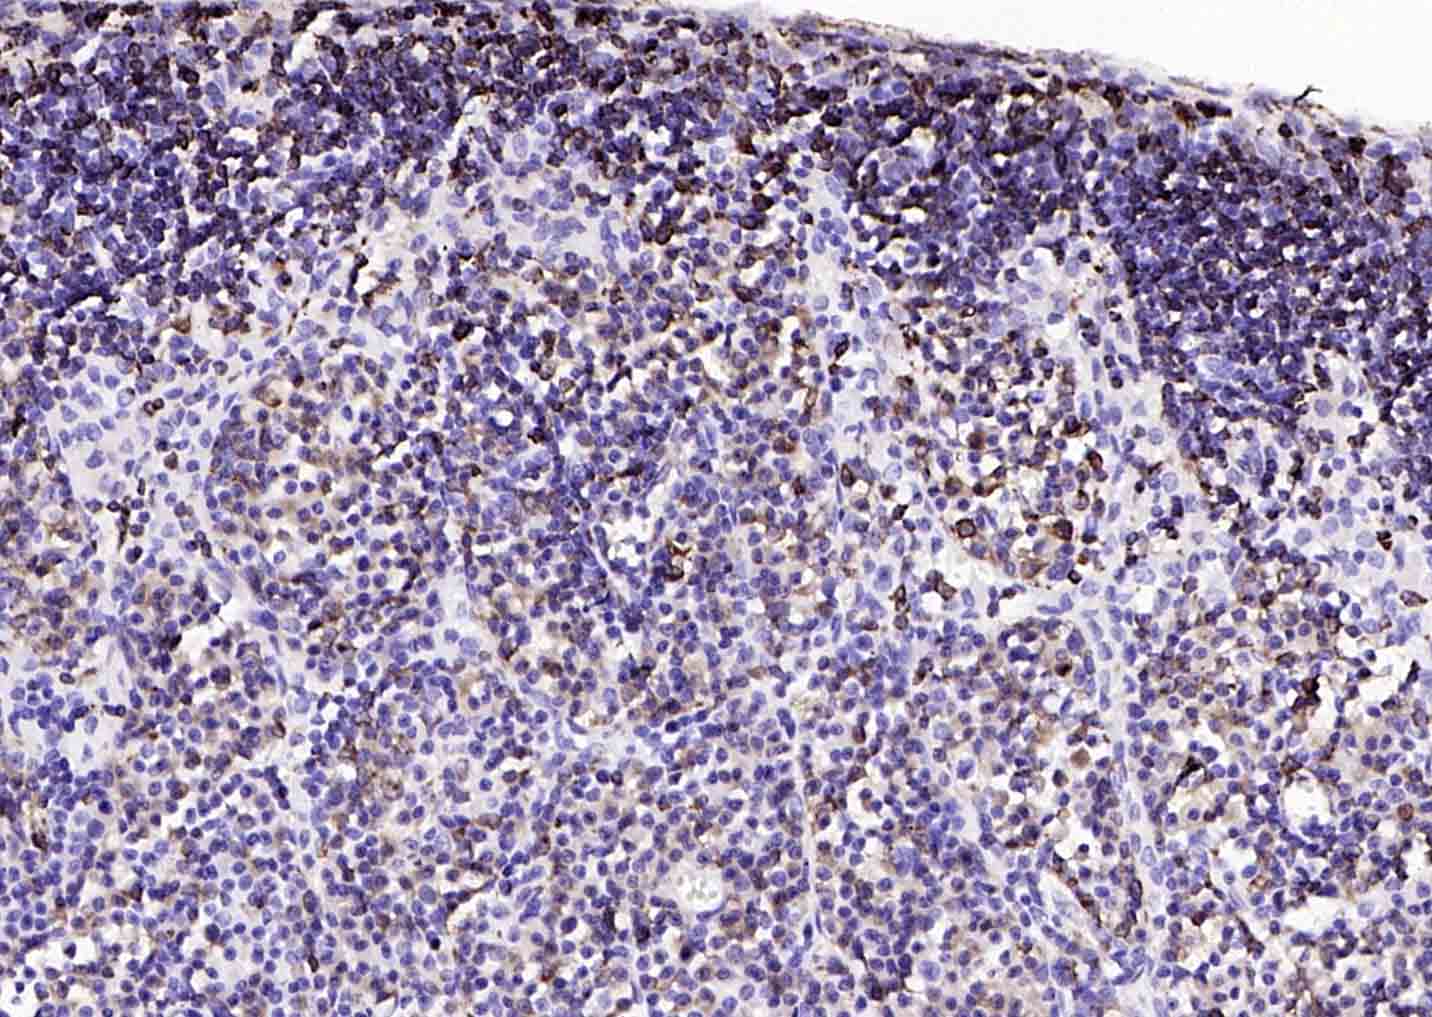

| 英文名称 | CD74 Rabbit pAb |

| 中文名称 | CD74抗体 |

| 产品应用 | IHC-P=1:100-500, IHC-F=1:100-500, IF=1:100-500, ELISA=1:5000-10000 Not yet tested in other applications. |

| 交叉反应 | Mouse |

| {IHC-P} | {1:100-500} |